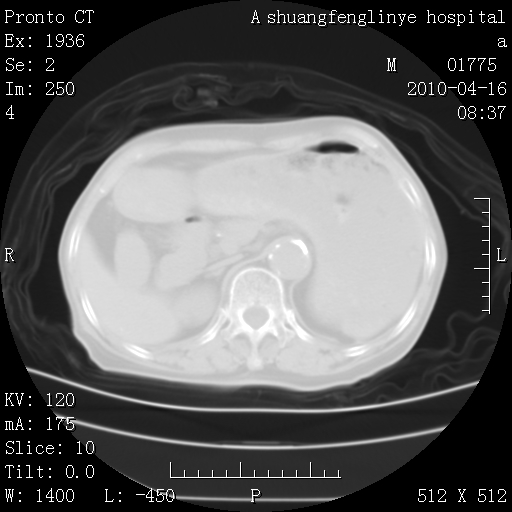

陈旧性结核,胃腔扩大,脾脏受压后移

慢支肺气肿,左上陈旧性结核,主动脉冠脉钙化